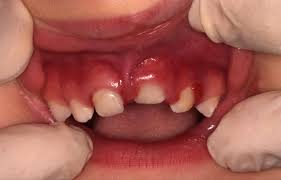

As luxações correspondem ao deslocamento do dente em relação à sua posição original no alvéolo e são divididas em três tipos principais:

- Intrusiva: O dente é deslocado para dentro do alvéolo, comprimindo as estruturas circundantes. Este tipo de luxação tem alto risco de necrose pulpar e reabsorção radicular. O tratamento pode incluir reposicionamento cirúrgico ou ortodôntico, dependendo da gravidade e da idade do paciente.

- Extrusiva: O dente é parcialmente deslocado para fora do alvéolo, mas mantém alguma conexão com os tecidos de suporte. O reposicionamento manual imediato, seguido de contenção, é essencial.

- Lateral: O deslocamento ocorre lateralmente, geralmente associado as fraturas do osso alveolar. O manejo envolve reposicionamento cuidadoso e contenção rígida para promover a estabilização e permitir a cicatrização óssea e periodontal.